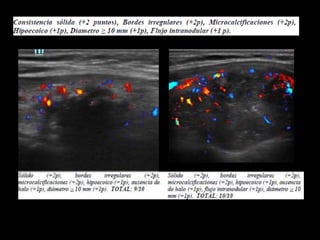

Este estudio desarrolló un modelo de predicción llamado "Alpha Score" para estimar el riesgo de malignidad en nódulos tiroideos basado en características ultrasonográficas. El estudio analizó 429 nódulos y encontró que características como hipoecogenicidad, solidez, bordes irregulares, microcalcificaciones y diámetro mayor a 10 mm estaban asociadas con malignidad. El modelo Alpha Score demostró ser una herramienta útil para estratificar el riesgo de malignidad en los nódulos y mejorar la